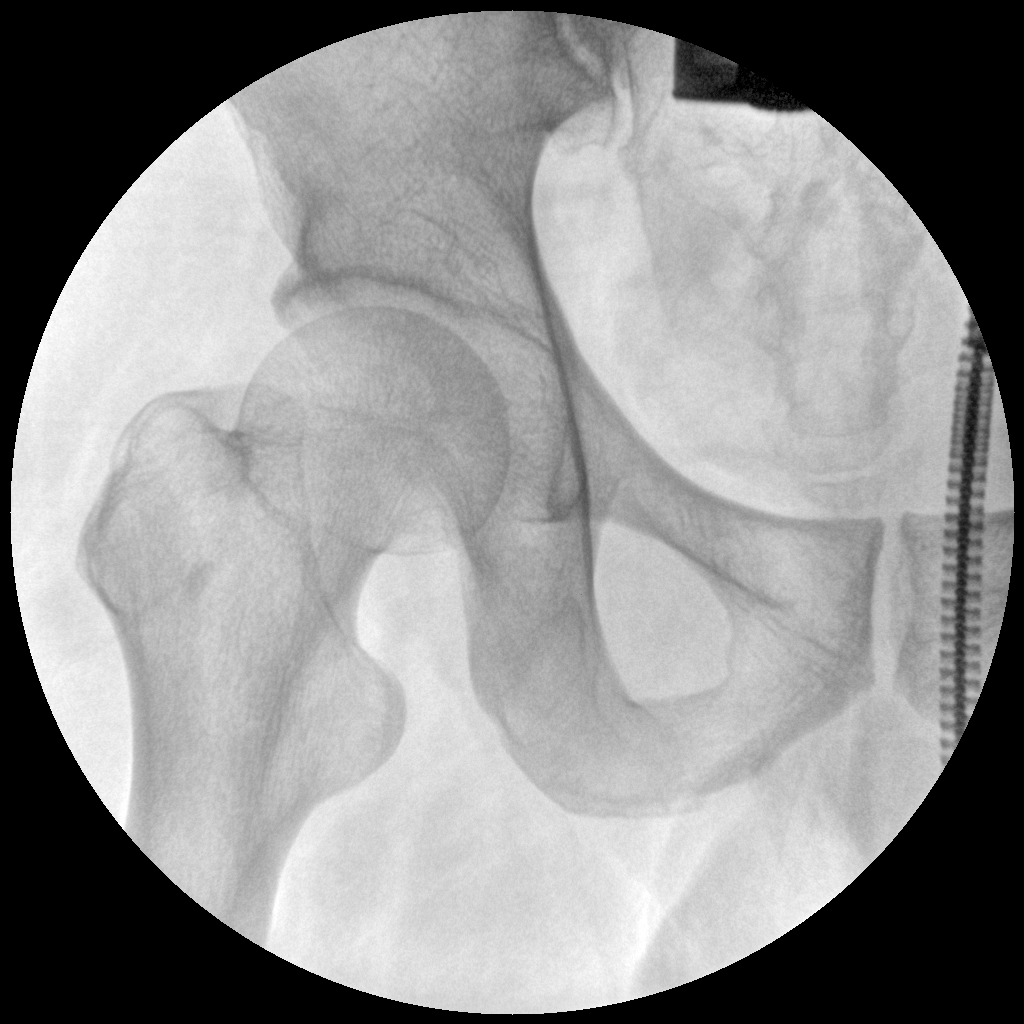

●全數(shù)字化百萬(wàn)像素影像系統(tǒng),圖像清晰

●靈活的C臂機(jī)架設(shè)計(jì),滿足臨床大范圍運(yùn)動(dòng)